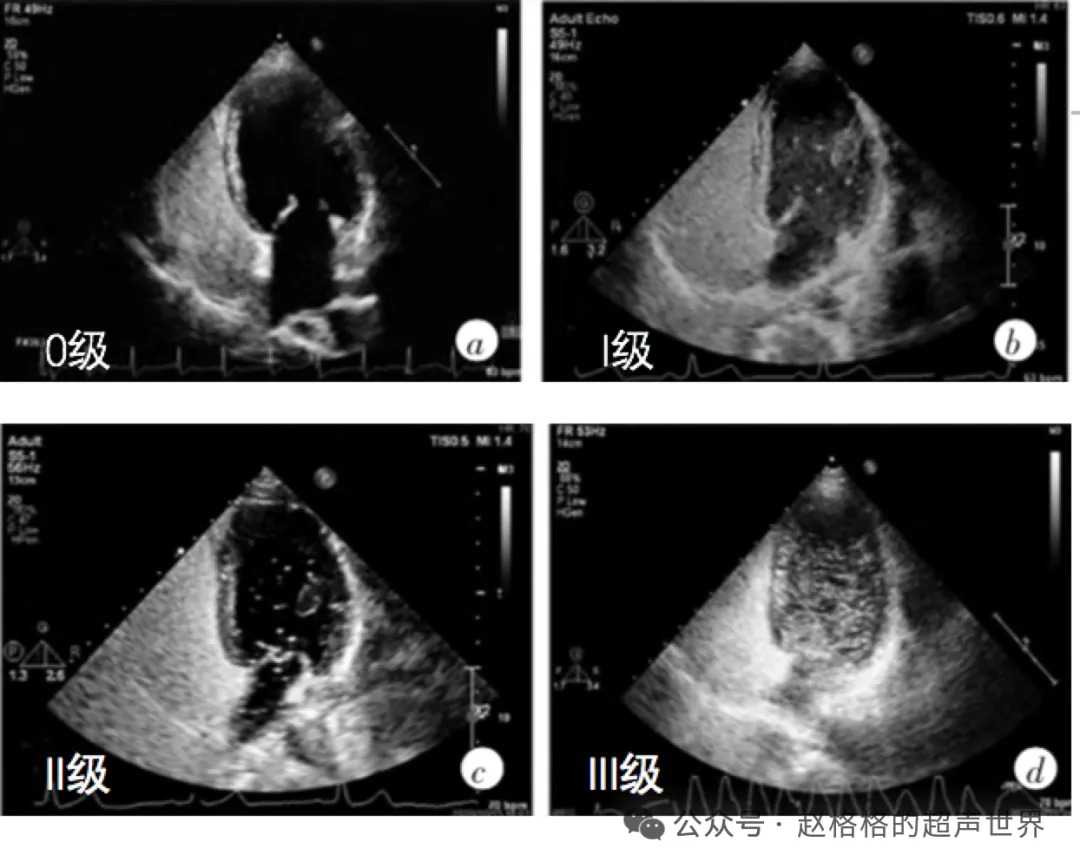

以静止单帧图像左心腔内出现的微泡的最大数量,将分流程度分为4级。

0 级:左心腔内没有微泡,无 RLS;

I级:左心腔内 1~10 个微泡/帧,为少量 RLS;

II级:左心腔内 10~30 个微泡/帧,为中量 RLS;

III级:左心腔内>30个微泡/帧,或左心腔几乎充满微泡,心腔浑浊,为大量 RLS